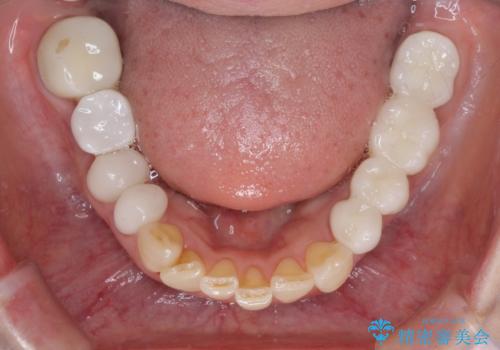

治療開始の日に欠損部も含めて仮歯が装着され、今までの不具合や不快感があっという間に改善されました。

抜歯部位の治癒を待つために時間がかかりましたが、来院回数は数回で済み、患者様には大変満足していただきました。